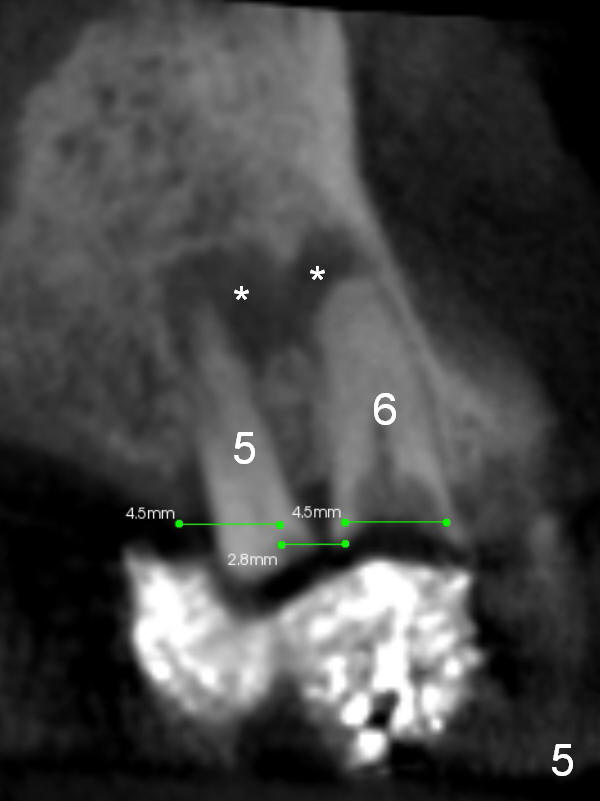

The patient prefers to have implant placement on the right side first. The implant at #5 should be placed a little more distal in order to have enough clearance (2-3 mm) between the implants at #5,6 (Fig.4 (thick section), 5 (thin section of CBCT)). Note the kissing periapical radiolucency at #5 and 6 (Fig.5 *). After residual root extraction, the sockets will be soaked with 2% Xylocaine/1:50,000 Epinephrine.

Fig.6,7 are coronal sections of the teeth #5 and 6, respectively. The buccal (B) plate is completely (Fig.6) or partially (Fig.7) lost. Osteotape is to be inserted between the buccal gingiva and the implant.